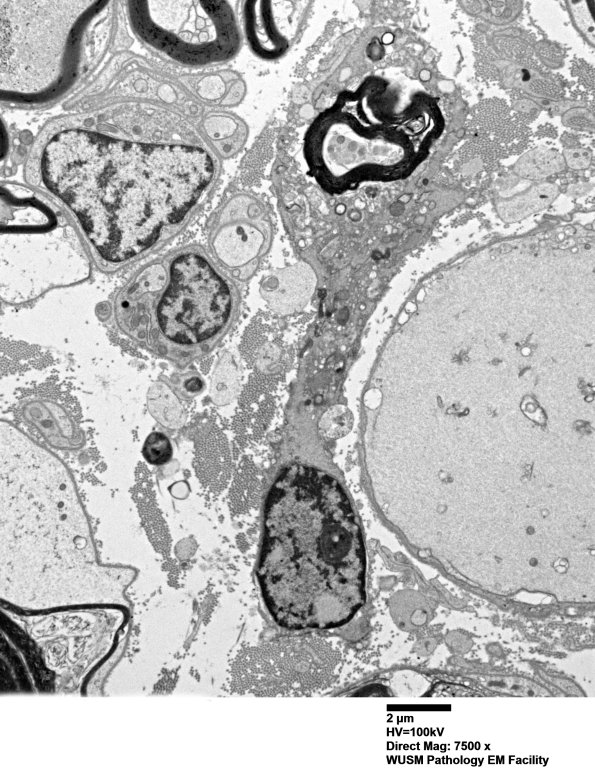

4F9A,B A macrophage with pseudopods surrounding a myelinated axon and adjacent to a large completely naked neurofilament containing axon. (electron micrographs)